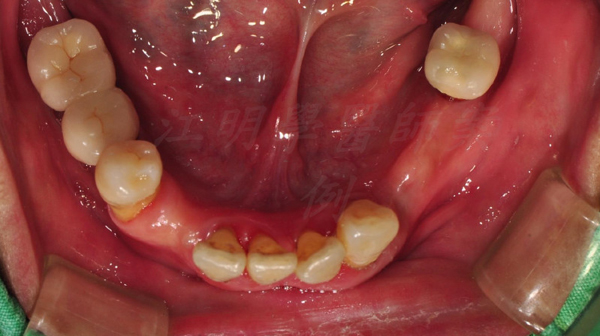

治療前